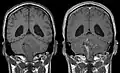

Épendymomes supratentoriels

Les épendymomes supratentoriels (SE) représentent entre 40% et 60% des tumeurs intracrâniennes. Localisées au niveau supratentoriel, ces tumeurs apparaissent comme des grosseurs peu homogènes, présentant des zones kystiques, des calcifications mais également des zones hémorragiques et nécrosées.

Aspect radiologique à l’IRM en séquence T1 après injection de Gadolinium d’un épendymome supratentoriel, caractérisé par une lésion bien délimitée du lobe frontal gauche avec prise de contraste hétérogène et des zones de nécrose.